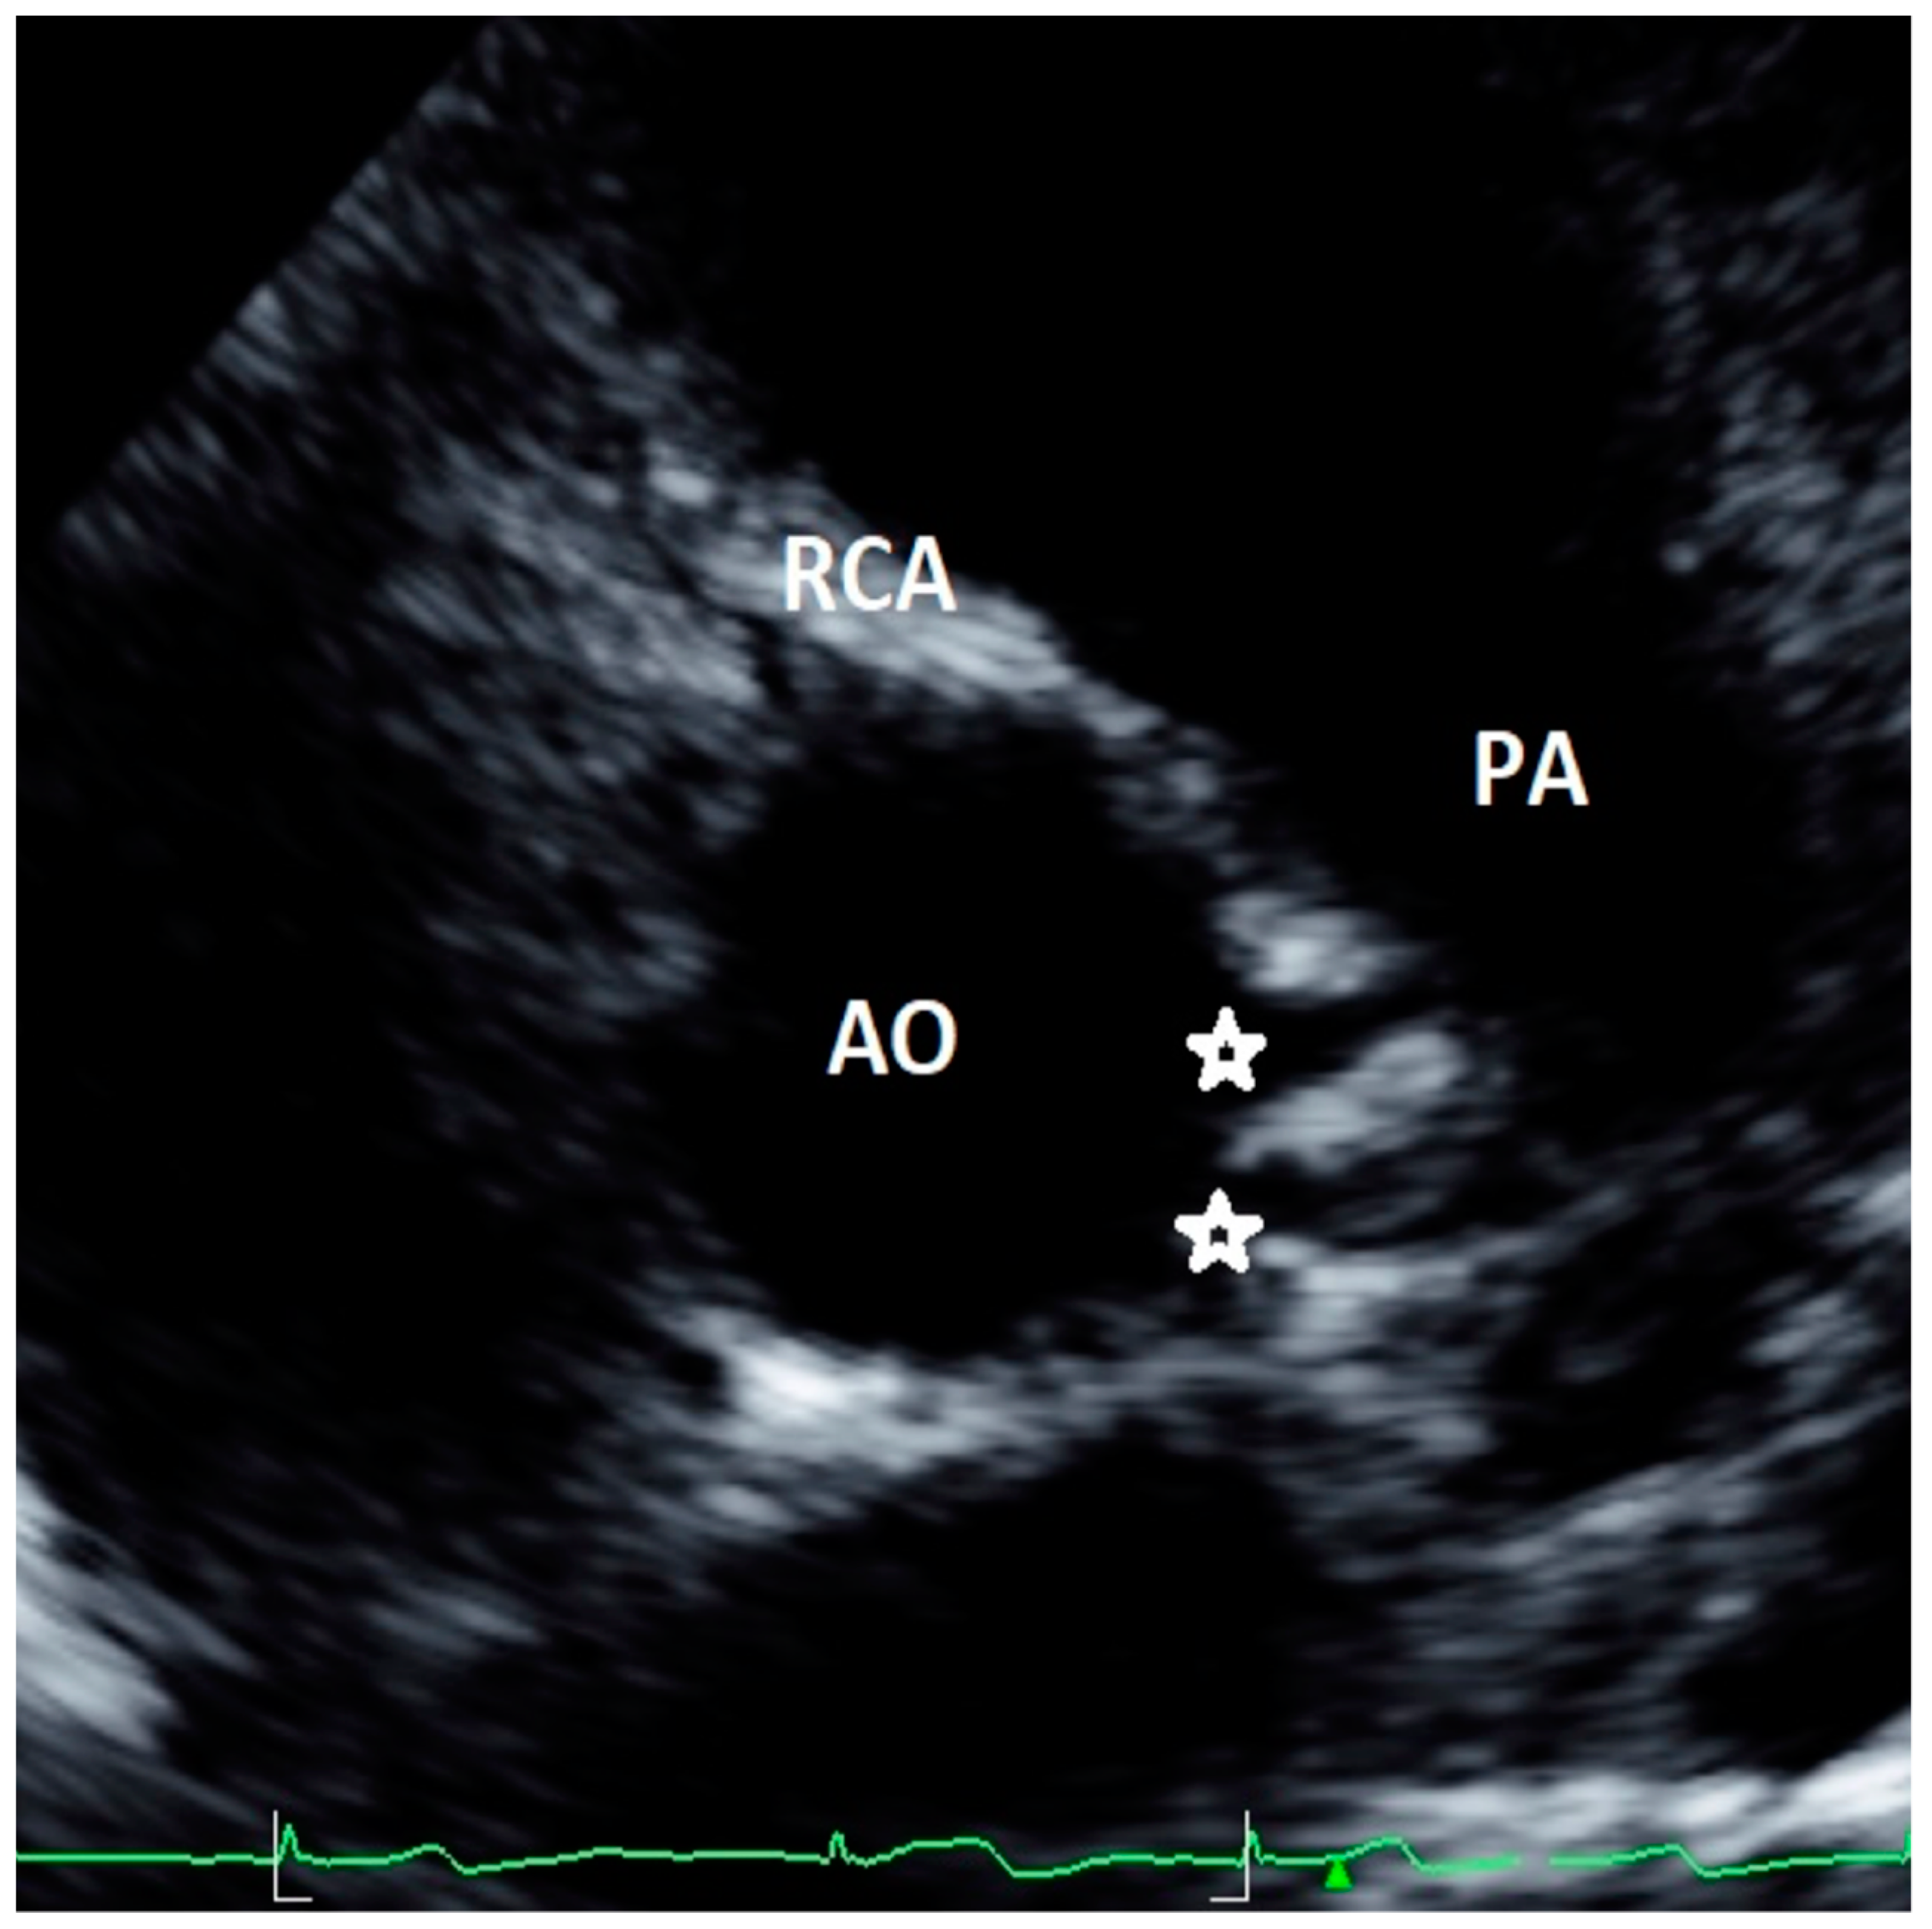

Figure 3. Asymptomatic 17-year-old boy evaluated for the presence of two premature ventricular beats at peak of stress test in routine preparticipation evaluation for sports competition. Parasternal long-axis view showing right coronary artery (RCA) high take-off coronary artery above the sinus of Valsalva (a). The acute angulation origin is clearly visualized in short-axis view (b) and was confirmed at CT (c). After CT confirmation of the defect, a myocardial scintigraphy was performed revealing a small ischemia (8%) in the RCA territory at peak. We advised sport restriction. Ao = aorta, LCA = left common coronary artery, RCA = right coronary artery, LSV = left sinus of Valsalva, RSV = right sinus of Valsalva. (d) is an example of 73-year-old man showing symptoms of dyspnea. 3D-Volume Rendering CCTA showing the right dominant coronary artery (RCA) high take-off two centimeters distal to the sinutubular junction at the level of the anterior ascending aortic wall.

3.6. Coronary Artery High Take-Off

High take-off coronary artery is a rare anomaly [33,34,35,36,37,38,39,40,41,42,43] that may present in isolation or associated with other congenital cardiac malformations [35,36,37,38,39,40,41,42,43], mainly identified for the RCAs (up to 84.46% of cases) [33]. There is still limited literature on the visualization and definition of RCA high take-off by echocardiography [13,14,23]; although there is not a consensus on the definition of high take-off by echocardiography, all the studies included in the present review defined high take-off as an origin above or distal to the sinutubular junction (STJ) [13,14,23]. An example of high take-off of RCA from our case series is reported in Figure 3. A very recent [13] study, of 1045 consecutive elite adolescent football players, identified coronary high take-off origin in 13 subjects (i.e., 1.14%). Eccentric RCA origin with a high take-off and partial intra-arterial course was observed in two cases (with no slit-like ostium and no intramural course); high take-off origin of the RCA with acute angle was observed in one case; high take-off of the RCA origin (with no intramural or slit-like orifice) was observed in 11 cases. Of the latter 11 cases, diagnosis was feasible only from the parasternal long-axis view, where the ostium of the RCA was measured from 2.3 to 6.8 mm above the sinutubular junction [13]. Lytrivi et al. [24] documented RCA high take-off in 53 cases (0.36%), LCA high take-off in four cases, and high take-off of both the coronary arteries in two cases of a valuable cohort of 14,546 pediatric subjects [23].